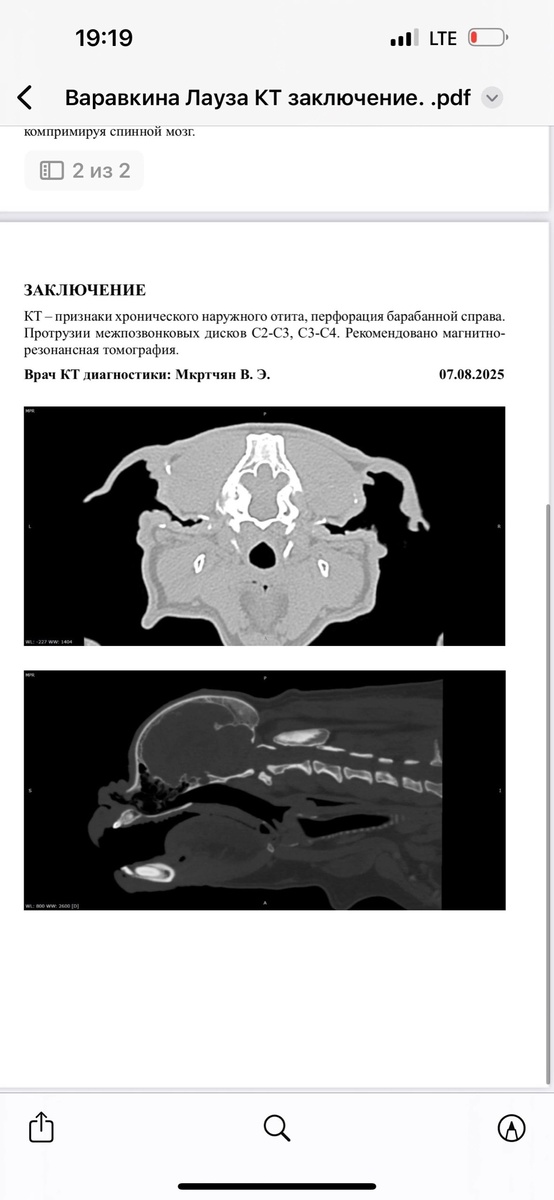

Дорогие друзья! #Лауза@frenchbull_help опять обращается к вам всем за помощью. Благодаря вам всем мы сделали Лаузе КТ, но результаты неутешительные: · Прободение барабанной перепонки, · Протрузии, · Искривление позвоночника (возможно, как у Волана). Врачи настоятельно рекомендуют провести МРТ для уточнения диагноза, а затем — консультацию у высококлассного хирурга. Чтобы дать Лаузе шанс на полноценную жизнь, мы приняли решение везти её из Кущёвской в Москву, где ей окажут лучшую помощь. Сегодня Лауза приехала в Москву. В воскресенье в 11ч у нее назначено МРТ, по его результату будет назначено дальнейшее лечение. Сегодня мы открываем срочный сбор Лаузе на: 🔸 МРТ-исследование, 🔸 Транспортировку (Кущёвская – Москва), 🔸 Консультацию и осмотр хирурга. Лауза — настоящий боец, но без вашей поддержки ей не справиться. Не оставайтесь в стороне! Вместе мы сможем всё! 🙏💔 👉 https://vk.cc/cOROhC

Благодаря вам всем мы сделали Лаузе КТ, но результаты неутешительные:

· Прободение барабанной перепонки,

· Протрузии,

· Искривление позвоночника (возможно, как у Волана).

Врачи настоятельно рекомендуют провести МРТ для уточнения диагноза, а затем — консультацию у высококлассного хирурга. Чтобы дать Лаузе шанс на полноценную жизнь, мы приняли решение везти её из Кущёвской в Москву, где ей окажут лучшую помощь.